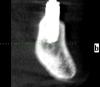

Wasja Опубликовано 10 декабря, 2012 Поделиться Опубликовано 10 декабря, 2012 Вот нарезка КТ Ссылка на комментарий

bullbull Опубликовано 27 марта, 2014 Поделиться Опубликовано 27 марта, 2014 Вот нарезка КТПри хорошем раскладе нижние простоят ещё несколько годков. А на счет верхних - сомневаюсь. Ссылка на комментарий